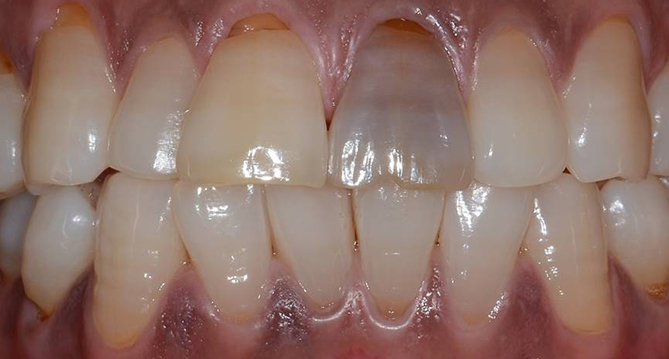

연세새빛치과 전체치아교정[클리피씨] 교정 전

연세새빛치과 전체치아교정[클리피씨] 교정 후